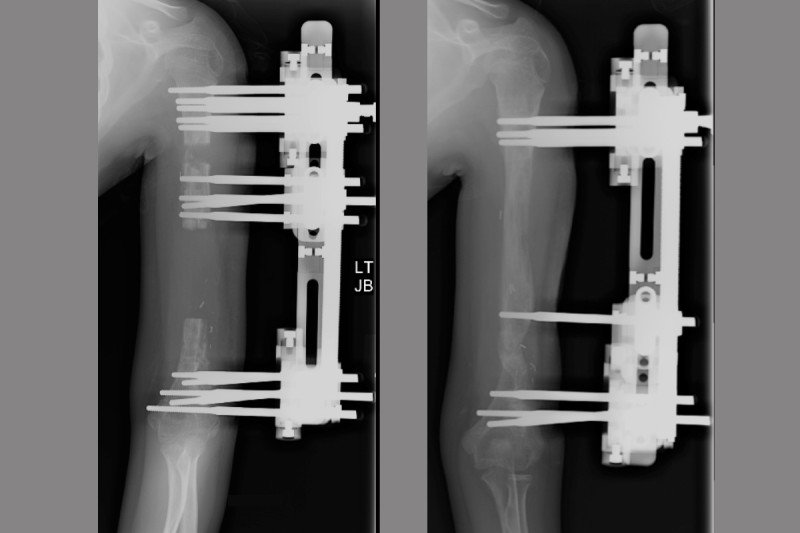

Pain caused by bone cancer usually begins with a feeling of tenderness in the affected bone. It also states that less than 0.2 percent of all cancers are primary bone cancers. If you feel a deep ache in your bone that doesn't go away, you may have bone cancer and you should go directly to bone cancer centers. One of the main symptoms of bone cancer is pain in the affected bone. Your red blood cell levels may drop, causing anemia. Bone cancer, especially in the leg may cause a limp over time as the pain increases and the body compensates. A limb amputation might be the only way to cure primary bone cancer for some people. In this tumor, the cancerous cells produce bone. It often grows worse over time. Pain in the affected bone is the most common sign of bone cancer. In rare circumstances, osteosarcomas can arise outside of bones (extraskeletal osteosarcomas). As bone cancer grows, it weakens the bone, which may cause a slight fracture, although this is a less common symptom. This variety of bone cancer occurs most often in children and young adults, in the bones of the leg or arm.

Depending on the cause, leg lumps may be single or multiple, soft or firm, painful or painless. Aggressive tumors can lead to disability or death, particularly. 3 with metastatic bone cancer, the spine is the most common area affected, and back pain is the most common symptom. This variety of bone cancer occurs most often in children and young adults, in the bones of the leg or arm. Any bone can be affected, although bone cancer most often develops in the long bones of the legs or upper arms. Localized leg pain can also be a sign of advanced cancer that has metastasized to the bones. A limb amputation might be the only way to cure primary bone cancer for some people. Bone tumors happen more often in people who've had radiation, stem cell transplants.